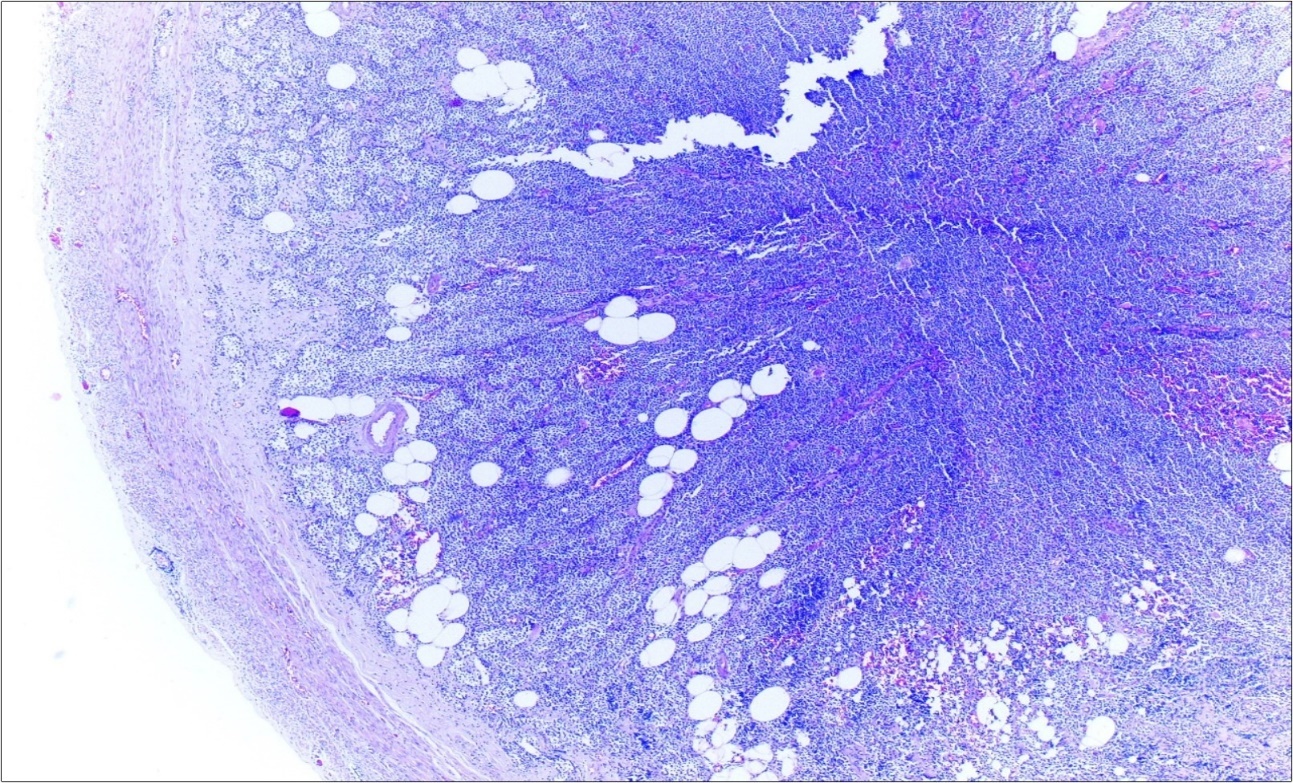

A 63-year-old woman presented to the Department of General Surgery as an outpatient with abdominal pain. Physical examination showed the signs of acute appendicitis and appendectomy was performed. During microscopic examination, a small focus of atypical monotonous lymphoid cell population was seen and the material was sampled totally. The pathological examination revealed MALT lymphoma (Figure 1), with diffuse positivity of cluster of differentiation (CD) 20 (Figure 2), CD 79a and B-cell lymphoma (Bcl- 2) (Figure 3) with just a few CD3 positive lymphoid cells. However, no evidence of adenocarcinoma was found in the appendectomy specimen. After the diagnosis of lymphoma, a complete colonoscopy was planned and this revealed a solid tumoral mass in the caecum measuring 5x4x4 cm. Computed tomography of the abdomen and pelvis revealed mesenteric lymphadenopathy associated with a mass in the caecum with multiple nodules in liver consistent with metastasis (Figure 4). Frozen sections were not obtained since the treatment method would not be affected. The patient underwent anterior resection with regional lymphadenectomy, with the pathological assessment of the resected specimen revealing a collision tumor consisting of a poorly differentiated adenocarcinoma extending through the muscularis propria with MALT lymphoma (Figure 5). Microscopic evaluation of the 11 regional lymph nodes in the mesentery of the resected colon and liver biopsy showed diffuse infiltration of MALT lymphoma with metastasis of adenocarcinoma (Figure 6). According to immunohistochemistry, atypical lymphocytes were positive for CD 20, Bcl-2, and negative for CD3, CD5, CD10, CD23, Bcl-6, terminal deoxynucleotidyl transferase, and cyclin D1. The proliferation fraction (MIB-1 immunostaining) was approximately 20%. The morphological and immunohistochemical findings were used to confirm the diagnosis of synchronous presentation of MALT lymphoma and colon adenocarcinoma within the caecum, mesenteric lymph nodes and liver metastases.

Figure 1.Appendix lumen infiltrated with B lymphoid cells (h&e;x100)